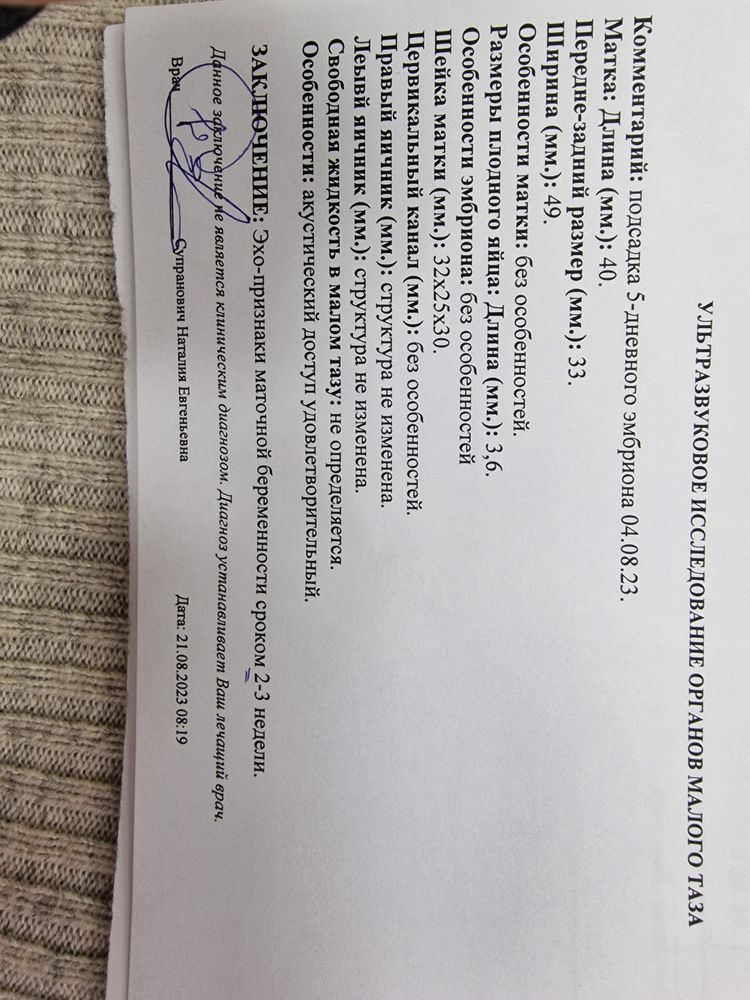

Вчера столько слез и истерик было из-за хгч... утром пошла на узи- там все нормально, никаких отслоек или проблем

Развивается

Но вчера хгч с 605 до 526 упал.

Врач даёт надежду, что такое бывает и может ещё вырасти